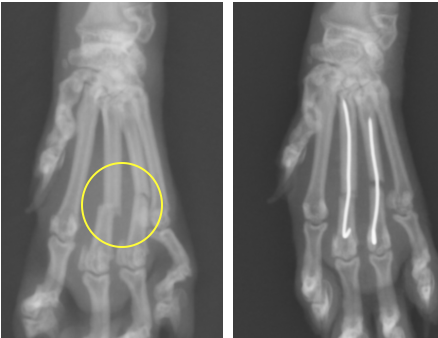

左第3指、第4指の骨折です。かなり小さい手のため、0.6mmという細いピンを使用しています。